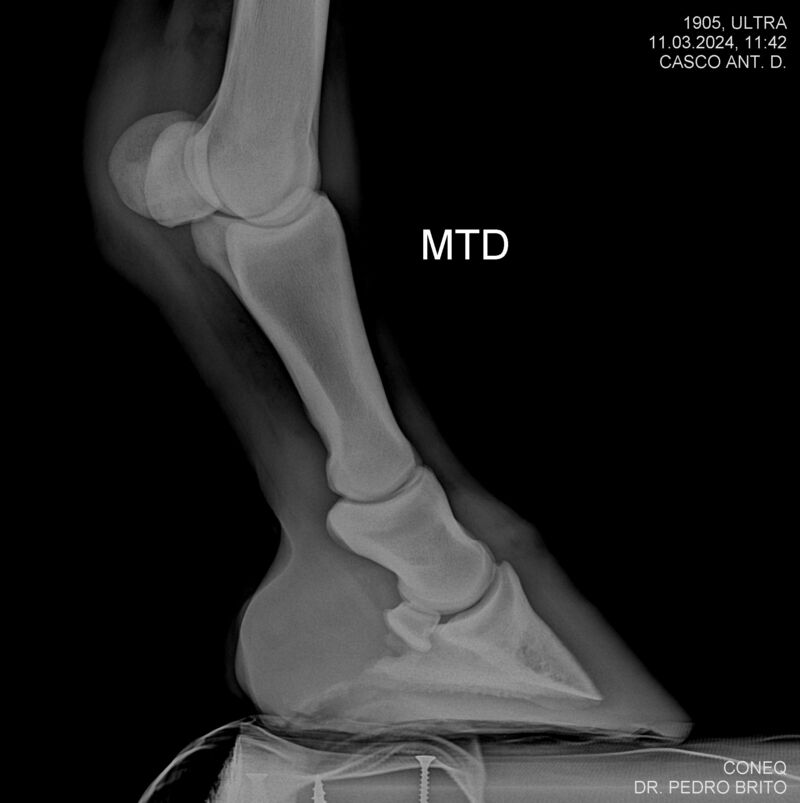

ULTRA DO CACH